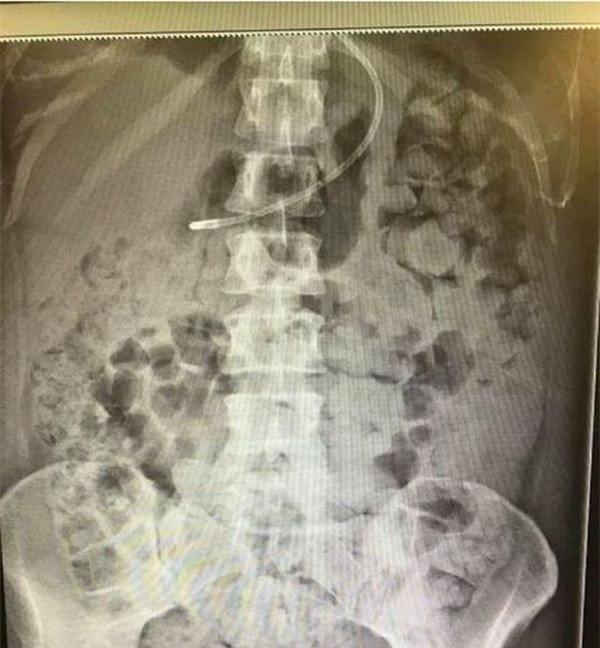

Vào đầu tháng 11 năm nay, cô có đăng tải lên mạng xã hội một bức hình chụp lại kết quả chụp X-quang của mình. Khi nhìn vào đó, người xem không thể tin được đó là hình ảnh X-quang của cơ thể người. “Chất thải” phủ kín phần ngực, cơ hoành và phổi của Kelly.

Hình ảnh chụp X-quang của Kelly